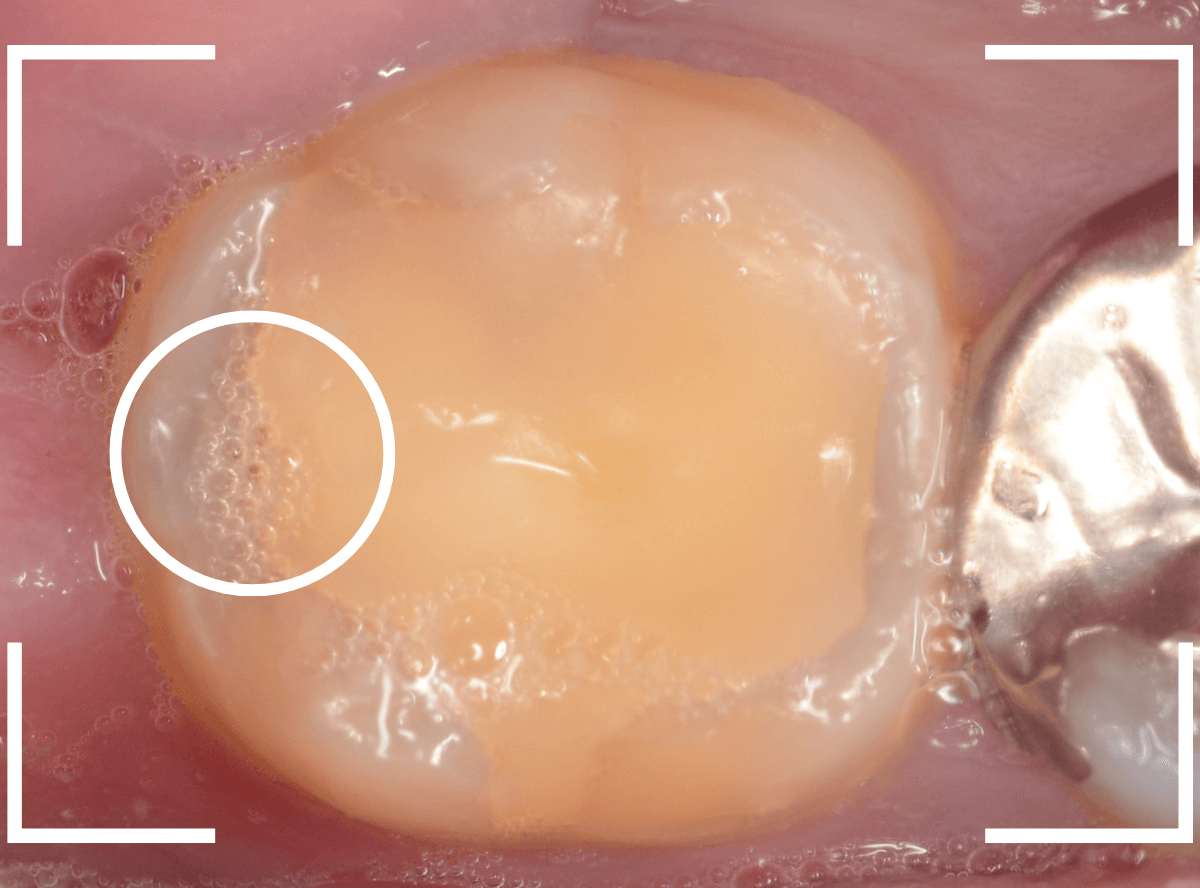

Case.6 上の奥歯の、見えづらいところで虫歯が進行!

こちらも上の一番奥の歯が深い虫歯になってしまった方です。

歯の頬側から奥側にかけて大きな虫歯になっているのがわかります。

カメラではうまく撮れましたが、実際は歯ブラシが届きづらく、虫歯になりやすいところです。

頬側の写真です。

ボコッと虫歯で穴が空いている状況ですが、本人には自覚症状がありません。

自覚症状がないから問題ないわけではない、というのがわかりますね。

治療を開始すると、大きな虫歯が出てきました。

虫歯を全て除去したところです。

赤い小さな点が見えているのは、歯の神経が少し見えてしまっている状態です。

運が悪ければ、神経を取る治療が必要になるかもしれません。

神経を保護するお薬をつめ、セメントで蓋をして、しばらく経過観察をします。

あとは痛みが出ないように祈ります。。。